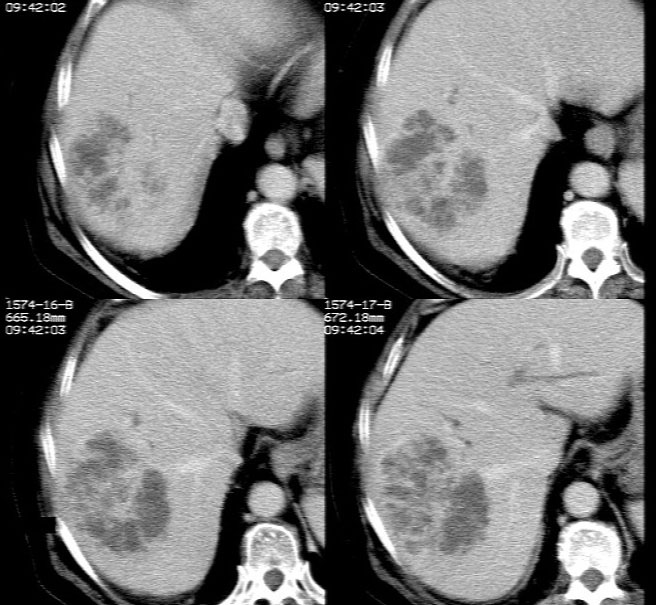

平扫示: 肝右后叶见团状低密度灶,边界欠清,密度略不均匀,ct值28-32hu,肝内胆管无扩张。

ct增强扫描示: 动脉期肝右后叶团状低密度边缘明显不均性强化,内呈不规则峰窝状低密度(无强化区),不规则分隔亦见明显强化;三期扫描像均见,病灶有明显占位征,周围血管、胆管推挤外移,病灶与正常肝组织分界不清,延迟期病灶周围见雾状略低密度(较肝左叶)。

肝右后叶团状低密度占位性病变,结合临床提示: 1、肝脓肿? 2、不排除肝ca可能。建议afp检查。

病灶三期明显强化,强化后边缘清楚,病灶内侧部分层面可见分层改变,支持考虑肝脓肿

病灶边缘及其内部分隔呈持续强化,考虑肝脓肿